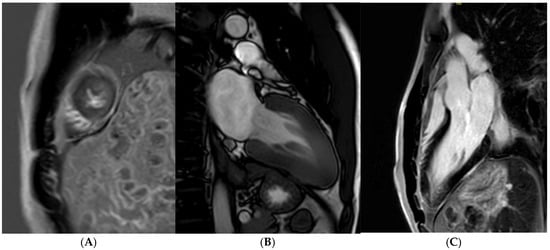

Small-vessel disease and microvascular dysfunction is a phenotypic trait in some HCM patients, often leading to a demand and supply perfusion mismatch in HCM patients (Figure 4) [58,76]. One small study also confirmed that coronary vasodilation reserve is preserved in athletes with physiological LV hypertrophy but reduced in patients with HCM [77], suggesting it may play a role when evaluating athletes in the grey zone. Data supporting routine ischaemia testing in athletes with HCM are inexistent. For HCM athletes who report chest pain without a documented LVOT obstruction (either at rest or during exercise) and epicardial coronary disease, our current practice is to perform perfusion imaging to specifically rule out microvascular dysfunction.

Figure 4. A 21 year old male that presented with chest pain during a pre-participation evaluation to join the armed forces. ECG showing biphasic ST segments in leads V1-V3, with T-wave inversion in II/III/aVF. CT coronary angiogram ruled out epicardial coronary disease. A stress echocardiogram ruled out dynamic LVOT obstruction. Echocardiogram confirmed the presence of hypertrophic cardiomyopathy, secondary to a likely pathogenic MYBPC3 variant. Cardiac MRI (3T scanner) showing septal hypertrophy (arrow) (A), extensive replacement (arrow) (B), and interstitial fibrosis in the septal segments (arrow) (C) (T1 map using a MOLLI 5b(3b)3b [3T]). Perfusion imaging (D) also identifying an extensive perfusion defect (arrow) in the hypertrophied segments, confirming microvascular dysfunction.